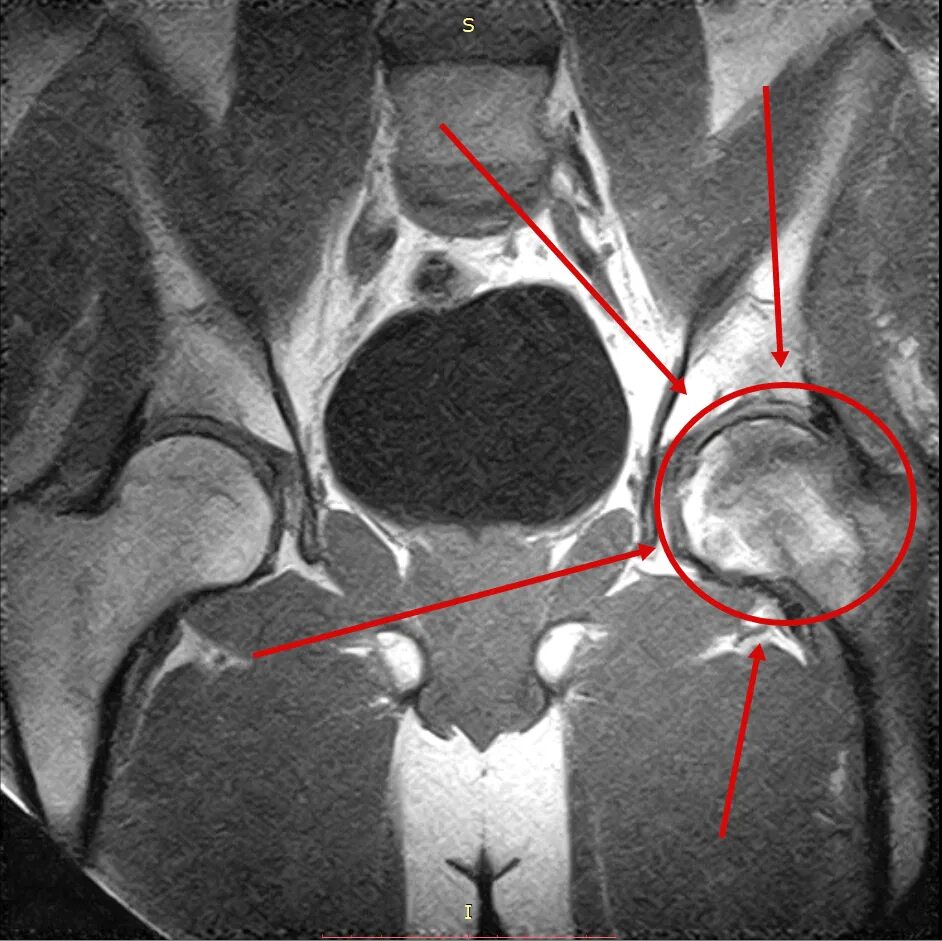

Метастазы в тазобедренном суставе